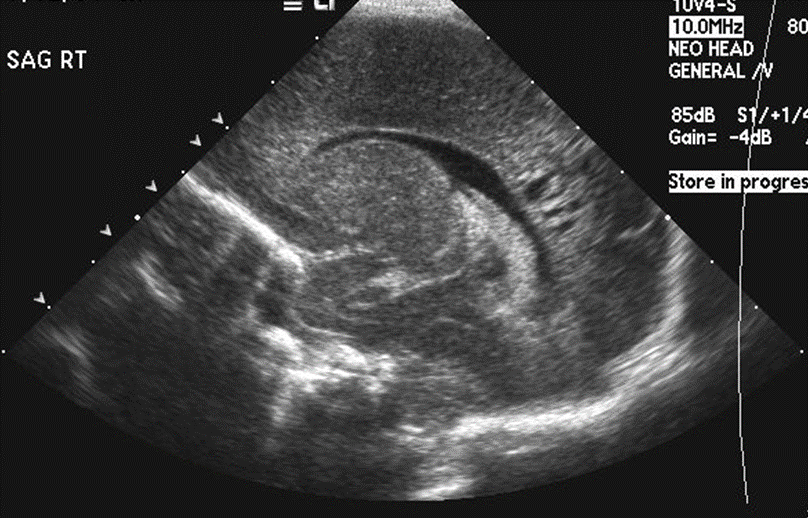

Brain

The brain is immature. [Yes/No]

There is under-sulcation and open sylvian fissures. [Yes/No]

Germinal matrix hemorrhage (Only in the premature infants): Please do not answer if the patient is a full term.

There is a germinal matrix hemorrhage, consistent with a grade I hemorrhage. [Yes/No]

There is an intraventricular extension consistent with a grade II hemorrhage. [Yes/No]

There is an intraventricular extension with the dilatation of ventricles, consistent with a grade III hemorrhage. [Yes/No]

There is an intra-parenchymal extension, consistent with grade IV hemorrhage. [Yes/No]